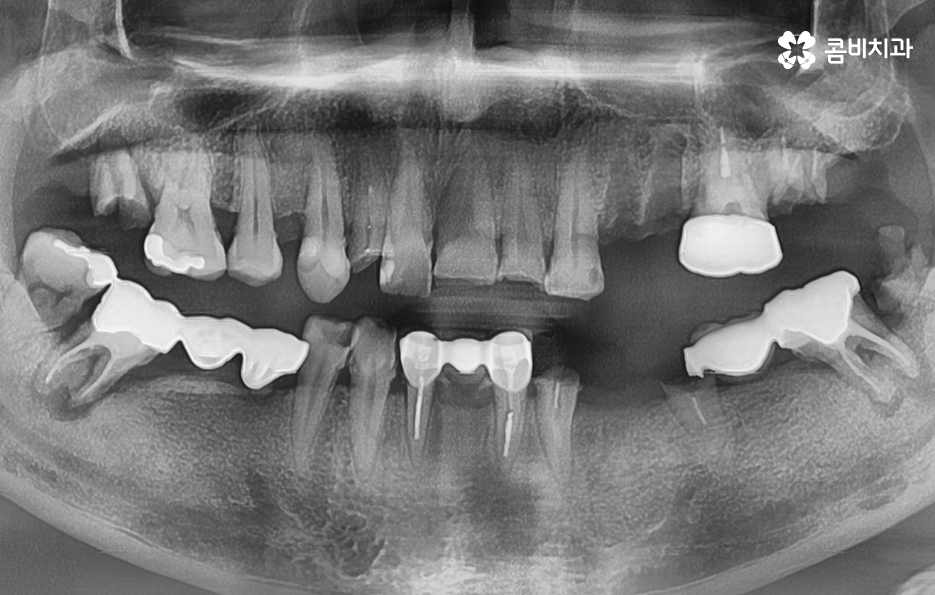

위 사진을 보시면 치아를 이미 잃은지 시간이 지난 상태의 치조골 즉 잇몸 뼈의 상태인 부위도 있고 어떤 치아는 거의 뿌리 부분만 남아 있으며 어떤 치아는 여러개의 보철물이 이어져 있는 상태인 경우도 있는데요

엑스레이 상태만 봐도 치아 저작 기능이 상당히 저하되어 있고 치아 상태가 매우 좋지 않음을 느낄 수 있을 정도인데 사실 임플란트를 필요로 하는 환자분들의 상당 수는 50대 이후부터 노년기에 치아 상실로 인한 임플란트의 필요성을 절실하게 느끼시는 분들이 많고 이미 여러 이유들로 인해 치아도 많이 발치된 경우도 있고 발치를 해야할 상황에서 임플란트를 알아보시는 분들이 많이 있어요

물론 30대 이전에도 치아를 잃게 되시는 분들도 많지만 일반적으로 40,50대 이전에는 충치나 사고로 인해 치아 하나 정도를 잃고 임플란트를 알아보시는 분들이 많고 잇몸이나 전신건강의 상태가 양호하신 분들이 많지만 50대 이후 특히 60대 이후에는 이미 치아를 잃고 시간이 지난 후에 임플란트를 하시는 분들과 치주염으로 인해 여러 치아를 잃게 되는 경우가 많기 때문에 위 엑스레이의 상태처럼 치아 뿐 아니라 잇몸 상태가 이미 안좋은 분들은 흔한 사례라고 할 수 있어요